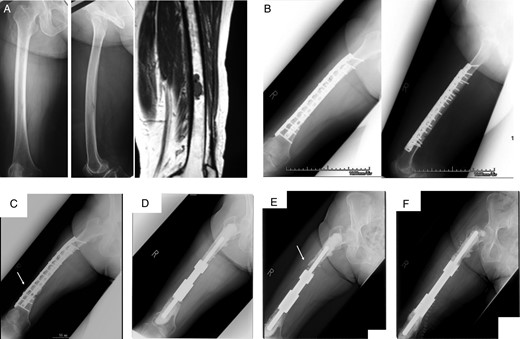

Case 2: A 71-year-old female was treated at the age of 68 for metastatic synovial sarcoma of the femur (Fig. 3A). Wide en bloc resection of the tumor and reconstruction with the use of IORBG were performed (Fig. 3B). At 32 months later, distal thigh pain due to fracture of the graft and breakage of plate occurred (Fig. 3C). Failed graft bone resection, implant removal and reconstruction with custom-made intercalary endoprosthesis were performed (Fig. 3D). The best MSTS score was 25 of 30. Aseptic loosening occurred at 29 months after the first endoprosthetic replacement which required a revision procedure (Fig. 3E and F). This was associated with osteolysis around the distal femoral end of the prosthesis.

A 68-year-old female with metastatic synovial sarcoma in right femoral diaphyseal bone. Plain radiograph and MRI (A) showing metastatic bone tumor. Radiograph (B) showing wide resection included femoral diaphyseal bone and reconstruction with IORBG and plate. At 32 months after surgery, radiograph (C) showing graft bone fracture (arrow) and reconstruction with intercalary endoprosthesis (D). Aseptic loosening occurred 29 months after surgery (E), and revision surgery was performed (F).